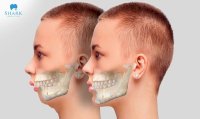

2.1 Giảm Tác Động Đến Khuôn Mặt

Niềng răng một hàm có thể giảm bớt sự thay đổi về khuôn mặt mà niềng răng toàn hàm thường tạo ra. Đối với những người có khuôn mặt nhạy cảm với sự thay đổi hoặc không muốn thấy sự thay đổi quá nhiều trong diện mạo của mình, việc niềng răng một hàm có thể là lựa chọn lý tưởng. Điều này giúp bệnh nhân cảm thấy thoải mái hơn với sự thay đổi nhỏ hơn trên khuôn mặt của họ.